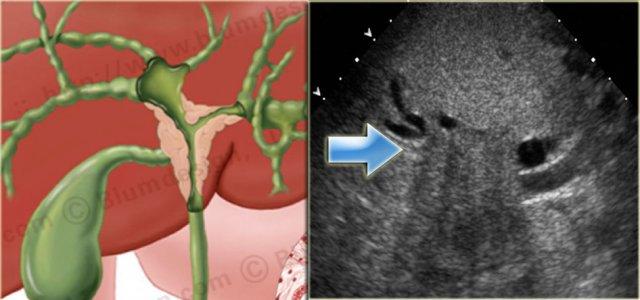

Bên trái là sự tương quan rõ nét giữa hình minh họa và hình ảnh siêu âm của u Klatskin.

Lưu ý ranh giới không rõ của khối u.

Trên CT, các khối u này có thể rất khó quan sát.

Nhiều bệnh nhân đã được đặt stent trước khi đến chụp CT, điều này càng làm cho việc phát hiện khối u trở nên khó khăn hơn (hình minh họa).